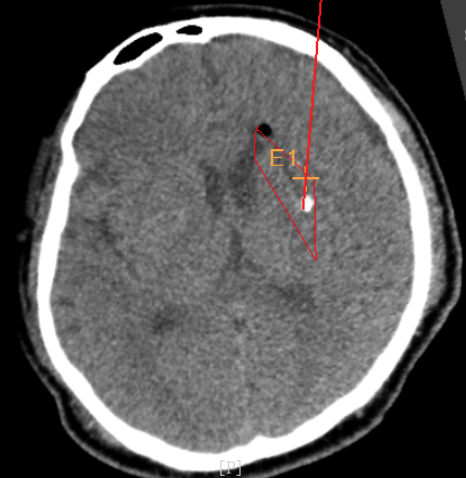

術(shù)前CT:血腫已經(jīng)液化,但仍有占位效應